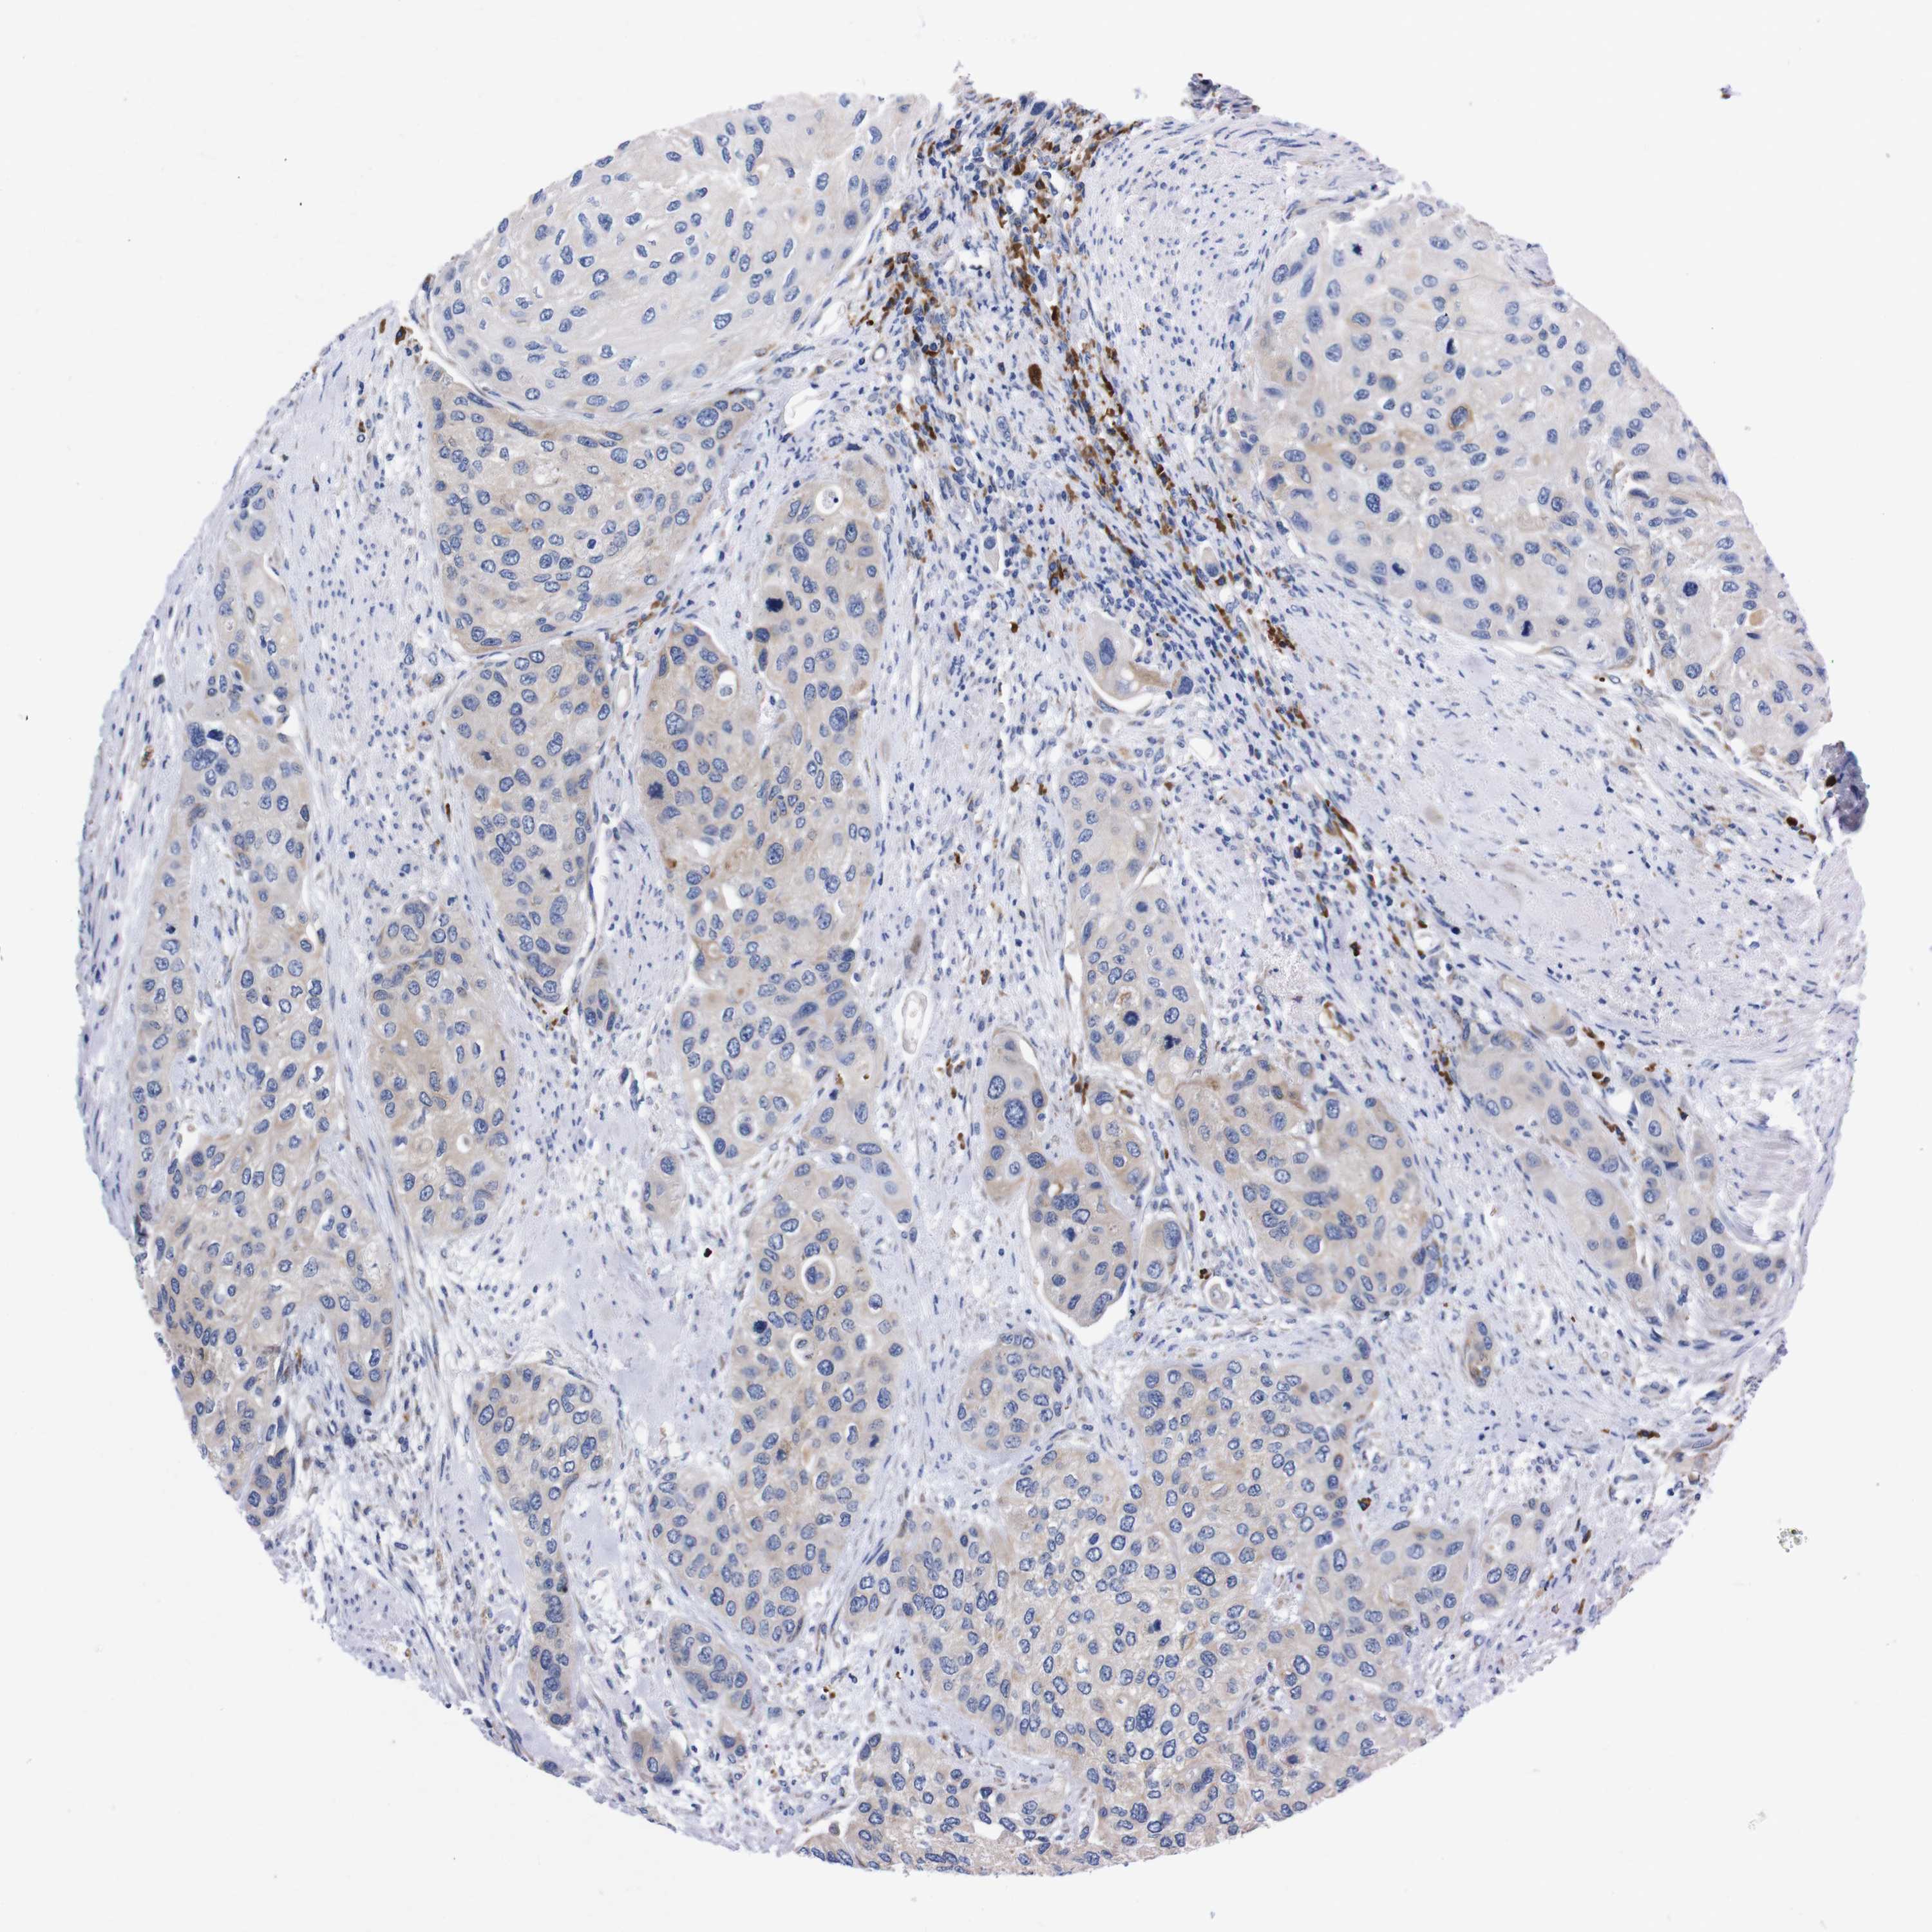

UROTHELIAL CANCER - Protein expressioni

A mouse-over function shows sample information and annotation data. Click on an image to view it in a full screen mode. Samples can be filtered based on level of antibody staining by selecting one or several of the following categories: high, medium, low and not detected. The assay and annotation is described here.

Note that samples used for immunohistochemistry by the Human Protein Atlas do not correspond to samples in the TCGA dataset.

Antibody stainingi

Antibody staining in the annotated cell types in the current human tissue is reported as not detected, low, medium, or high, based on conventional immunohistochemistry profiling in selected tissues. This score is based on the combination of the staining intensity and fraction of stained cells.

Each image is clickable and will lead to virtual microscopy that enables deeper exploration of all samples and also displays staining intensity scores, fraction scores and subcellular localization as well as patient and tissue information for each sample.

Antibody HPA013994

Antibody HPA013995

Staining

High

Medium

Low

Not detected

Intensity

Strong

Moderate

Weak

Negative

Quantity

>75%

75%-25%

<25%

None

Location

Nuclear

Cytoplasmic/membranous

Cytoplasmic/membranous,nuclear

Urothelial carcinoma, Low grade

Urothelial carcinoma, High grade